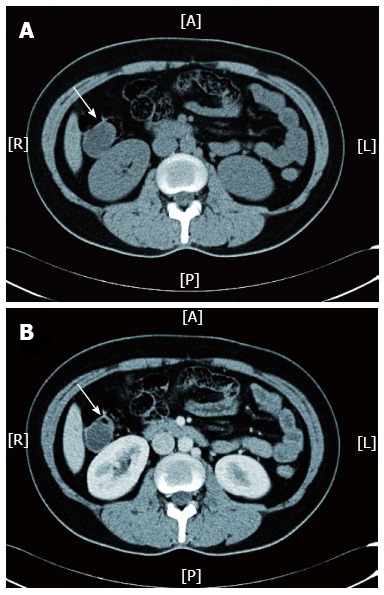

图2

病例 1 的腹部盆腔计算机断层扫描显示升结肠处有一个囊性肿块(白色箭头所示),在非造影扫描 (A) 中可见,但在动脉期后未增强 (B)。 A:前部; R:右; L:左; 普:后部。